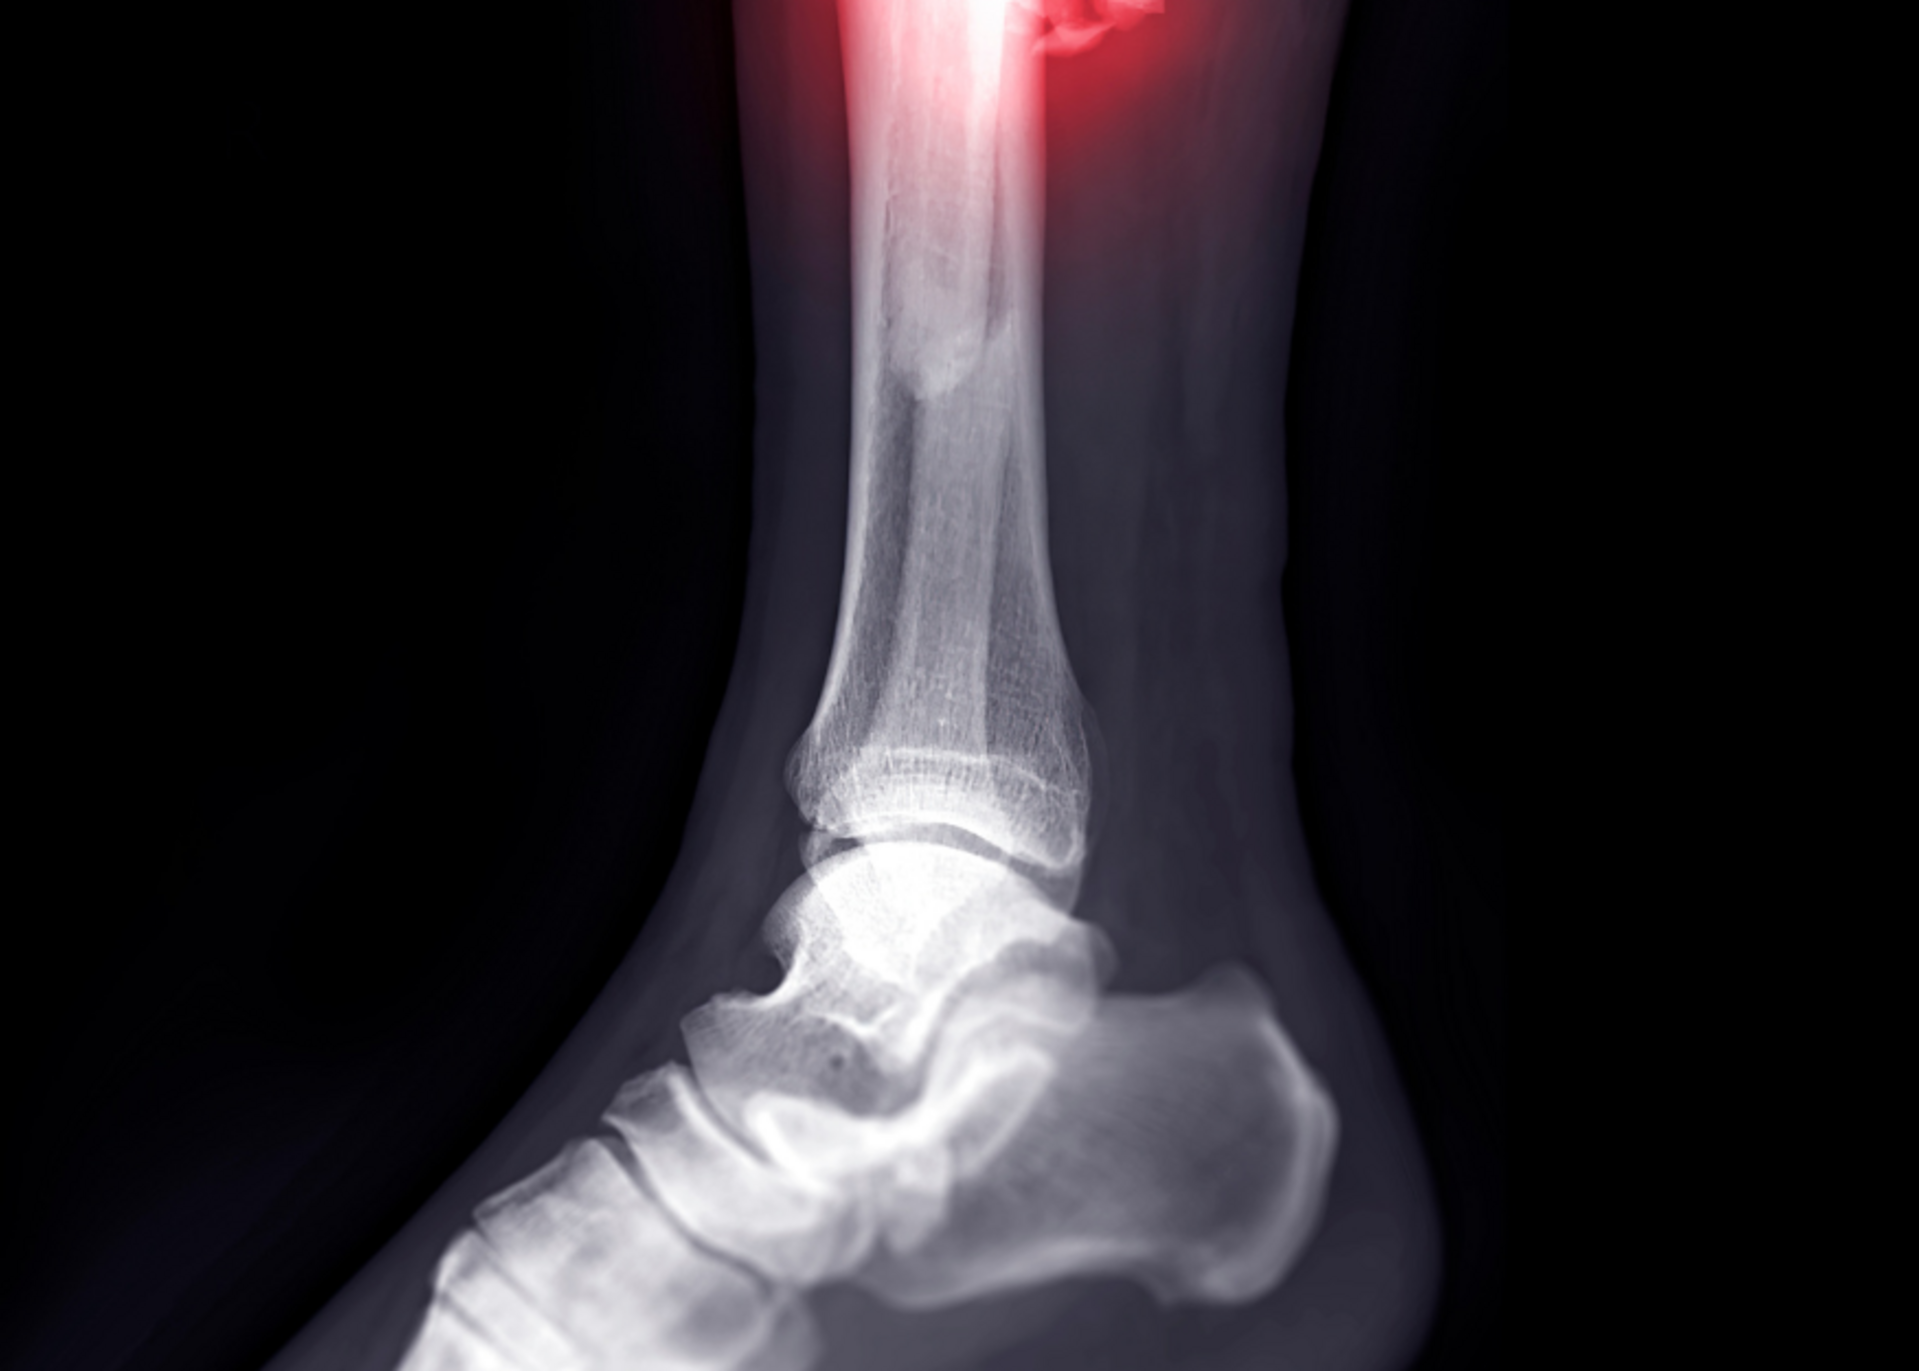

Fracture Management in Palam Vihar, Gurugram

Fractures, or broken bones, are among the most common orthopedic injuries affecting people of all ages. Whether caused by trauma, falls, sports inj...